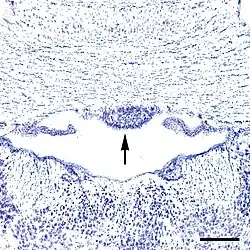

The subfornical organ (SFO) is one of the circumventricular organs of the brain.[1][2] Its name comes from its location on the ventral surface of the fornix near the interventricular foramina (foramina of Monro), which interconnect the lateral ventricles and the third ventricle. Like all circumventricular organs, the subfornical organ is well-vascularized, and like all circumventricular organs except the subcommissural organ, some SFO capillaries have fenestrations, which increase capillary permeability.[1][3][4] The SFO is considered a sensory circumventricular organ because it is responsive to a wide variety of hormones and neurotransmitters, as opposed to secretory circumventricular organs, which are specialized in the release of certain substances.[1][4][5]

As noted above, capillaries in some subregions within the SFO are fenestrated,[6] and thus lack a blood–brain barrier. All circumventricular organs except the subcommissural organ contain fenestrated capillaries,[2] a feature that distinguishes them from most other parts of the brain.[7] The SFO can be divided into six anatomical zones based on its capillary topography: two zones in the coronal plane and four zones in the sagittal plane.[3] The central zone is composed of the glial cells, neuronal cell bodies and a high density of fenestrated capillaries.[8] Conversely, the rostral and caudal areas have a lower density of capillaries[8] and are mostly made of nerve fibers, with fewer neurons and glial cells seen in this area. Functionally, however, the SFO may be viewed in two portions, the dorsolateral peripheral division, and the ventromedial core segment.[9]